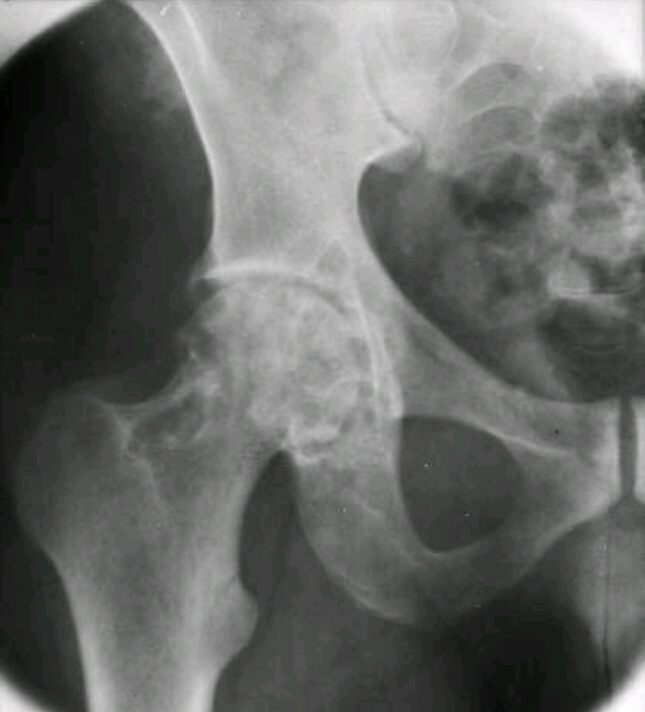

This is a 17 year old boy with hip pain and he doesn’t know where it came from. What is the disease?

pigmented villonodular synovitis